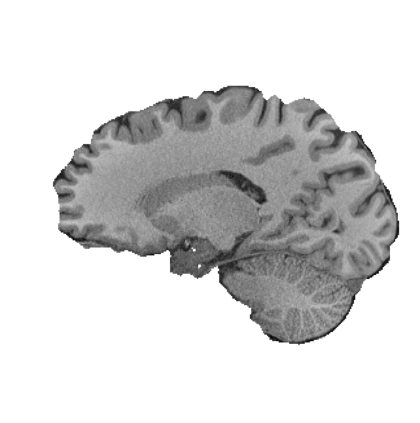

Magnetic resonance (MR) images are often acquired in 2D settings for real clinical applications. The 3D volumes reconstructed by stacking multiple 2D slices have large inter-slice spacing, resulting in lower inter-slice resolution than intra-slice resolution. Super-resolution is a powerful tool to reduce the inter-slice spacing of 3D images to facilitate subsequent visualization and computation tasks. However, most existing works train the super-resolution network at a fixed ratio, which is inconvenient in clinical scenes due to the heterogeneous parameters in MR scanning. In this paper, we propose a single super-resolution network to reduce the inter-slice spacing of MR images at an arbitrarily adjustable ratio. Specifically, we view the input image as a continuous implicit function of coordinates. The intermediate slices of different spacing ratios could be constructed according to the implicit representation up-sampled in the continuous domain. We particularly propose a novel local-aware spatial attention mechanism and long-range residual learning to boost the quality of the output image. The experimental results demonstrate the superiority of our proposed method, even compared to the models trained at a fixed ratio.

翻译:磁共振图像通常在 2D 环境中获得,用于真正的临床应用。通过堆叠多个 2D 切片重建的 3D 体积具有很大的切片间距,导致切片间分辨率低于切片分辨率。超级分辨率是减少3D 图像间隔的有力工具,以便利随后的可视化和计算任务。然而,大多数现有工程都以固定比例对超级分辨率网络进行培训,这在临床场景中不方便,因为MR 扫描的参数各异。在本文中,我们提议建立一个单一的超级分辨率网络,以任意调整比例降低MR 图像的切片间间间距。具体地说,我们将输入图像视为坐标的一个连续的隐含功能。不同间距比率的中间切片可以按照连续域内隐含的显示比例来构造。我们特别提议了一个新的地方觉空间关注机制和远程留置学习,以提高输出图像的质量。实验结果显示我们拟议方法的优越性,即使与所培训的模型相比,也是一种固定比例。